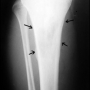

Kemik üreten selim bir kemik tümörüdür. Sıklıkla 10 - 20 yaşları arasındaki erkeklerde görülür. Ana şikayet zonklayıcı, genellikle geceleri artan ve uykudan uyandırabilen, aspirin ile geçebilen bir ağrıdır. Bazı hastalar, ağrı nedeni ile uzvunu kullanamama, buna bağlı eklem hareket kısıtlılığı ve şekil bozukluğu (kontraktür), uzuvda incelme, omurgada eğrilik gibi şikayetler ile başvurur. En sık femur boynunda ve tibiada olmakla birlikte tür kemiklerde ortaya çıkabilir. Lezyonun karakteristik özelliği düz grafide litik görülen bir çekirdek (nidus) ve bunun etrafında yoğun kemik oluşumu ile karakterize sklerotik bir halkadır. MRG, nidus çevresinde ve bazen yumuşak dokuya taşan ödemi abartarak gösterdiği için çoğu zaman daha korkutucu tanıları düşündürebilir. Sintigrafi odaksal bir tutulum ve ortasında tutulum olmayan bir nokta gösterecektir. Osteoid osteoma için en değerli ve hassas tanı koydurucu yöntem, bilgisayarlı tomografidir. İnce kesitli (en fazla 2 mm) BT incelemesinde nidus ve çevresindeki skleroz tipik olarak gösterilebilir.

Çok uzun süreli NSAID ile tedavi edilebilen vakalar bildirilse de bu diğer yan etkileri ve çok düşük başarı ihtimali nedeniyle tercih edilmemelidir. Tercih edilecek yöntem nidusun uzaklaştırılmasıdır. Cerrahi yöntemle bu bölgenin bulunup nidusun çıkartılması ve çevresinin tur aleti ile alınması yeterlidir. BT altında bu bölgeye ulaşılarak radyofrekans cihazı ile nidusun yakılması yeni uygulanmaya başlanan ve başarı oranı henüz değerlendirilememiş bir yöntemdir. Açık cerrahi (ameliyat) halen "altın standart" yöntem olup patolojik inceleme için görerek yeterli materyal alınmasına da imkan sağlar.